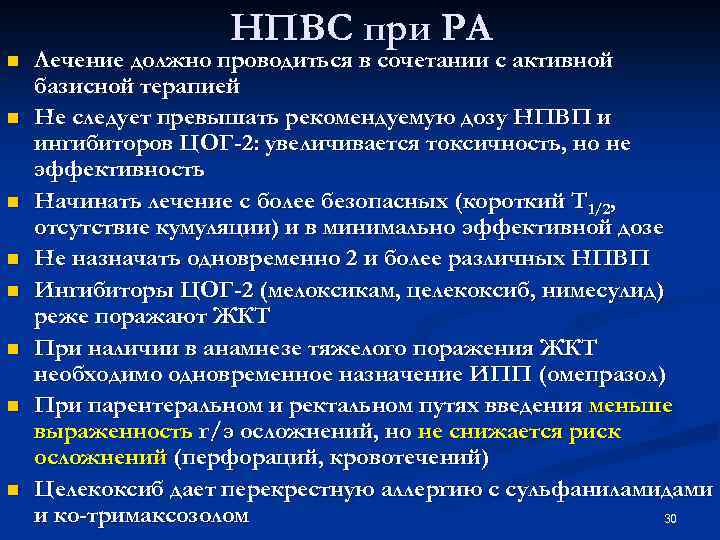

n n n n НПВС при РА Лечение должно проводиться в сочетании с активной базисной терапией Не следует превышать рекомендуемую дозу НПВП и ингибиторов ЦОГ-2: увеличивается токсичность, но не эффективность Начинать лечение с более безопасных (короткий Т 1/2, отсутствие кумуляции) и в минимально эффективной дозе Не назначать одновременно 2 и более различных НПВП Ингибиторы ЦОГ-2 (мелоксикам, целекоксиб, нимесулид) реже поражают ЖКТ При наличии в анамнезе тяжелого поражения ЖКТ необходимо одновременное назначение ИПП (омепразол) При парентеральном и ректальном путях введения меньше выраженность г/э осложнений, но не снижается риск осложнений (перфораций, кровотечений) Целекоксиб дает перекрестную аллергию с сульфаниламидами и ко-тримаксозолом 30

n n n n НПВС при РА Лечение должно проводиться в сочетании с активной базисной терапией Не следует превышать рекомендуемую дозу НПВП и ингибиторов ЦОГ-2: увеличивается токсичность, но не эффективность Начинать лечение с более безопасных (короткий Т 1/2, отсутствие кумуляции) и в минимально эффективной дозе Не назначать одновременно 2 и более различных НПВП Ингибиторы ЦОГ-2 (мелоксикам, целекоксиб, нимесулид) реже поражают ЖКТ При наличии в анамнезе тяжелого поражения ЖКТ необходимо одновременное назначение ИПП (омепразол) При парентеральном и ректальном путях введения меньше выраженность г/э осложнений, но не снижается риск осложнений (перфораций, кровотечений) Целекоксиб дает перекрестную аллергию с сульфаниламидами и ко-тримаксозолом 30